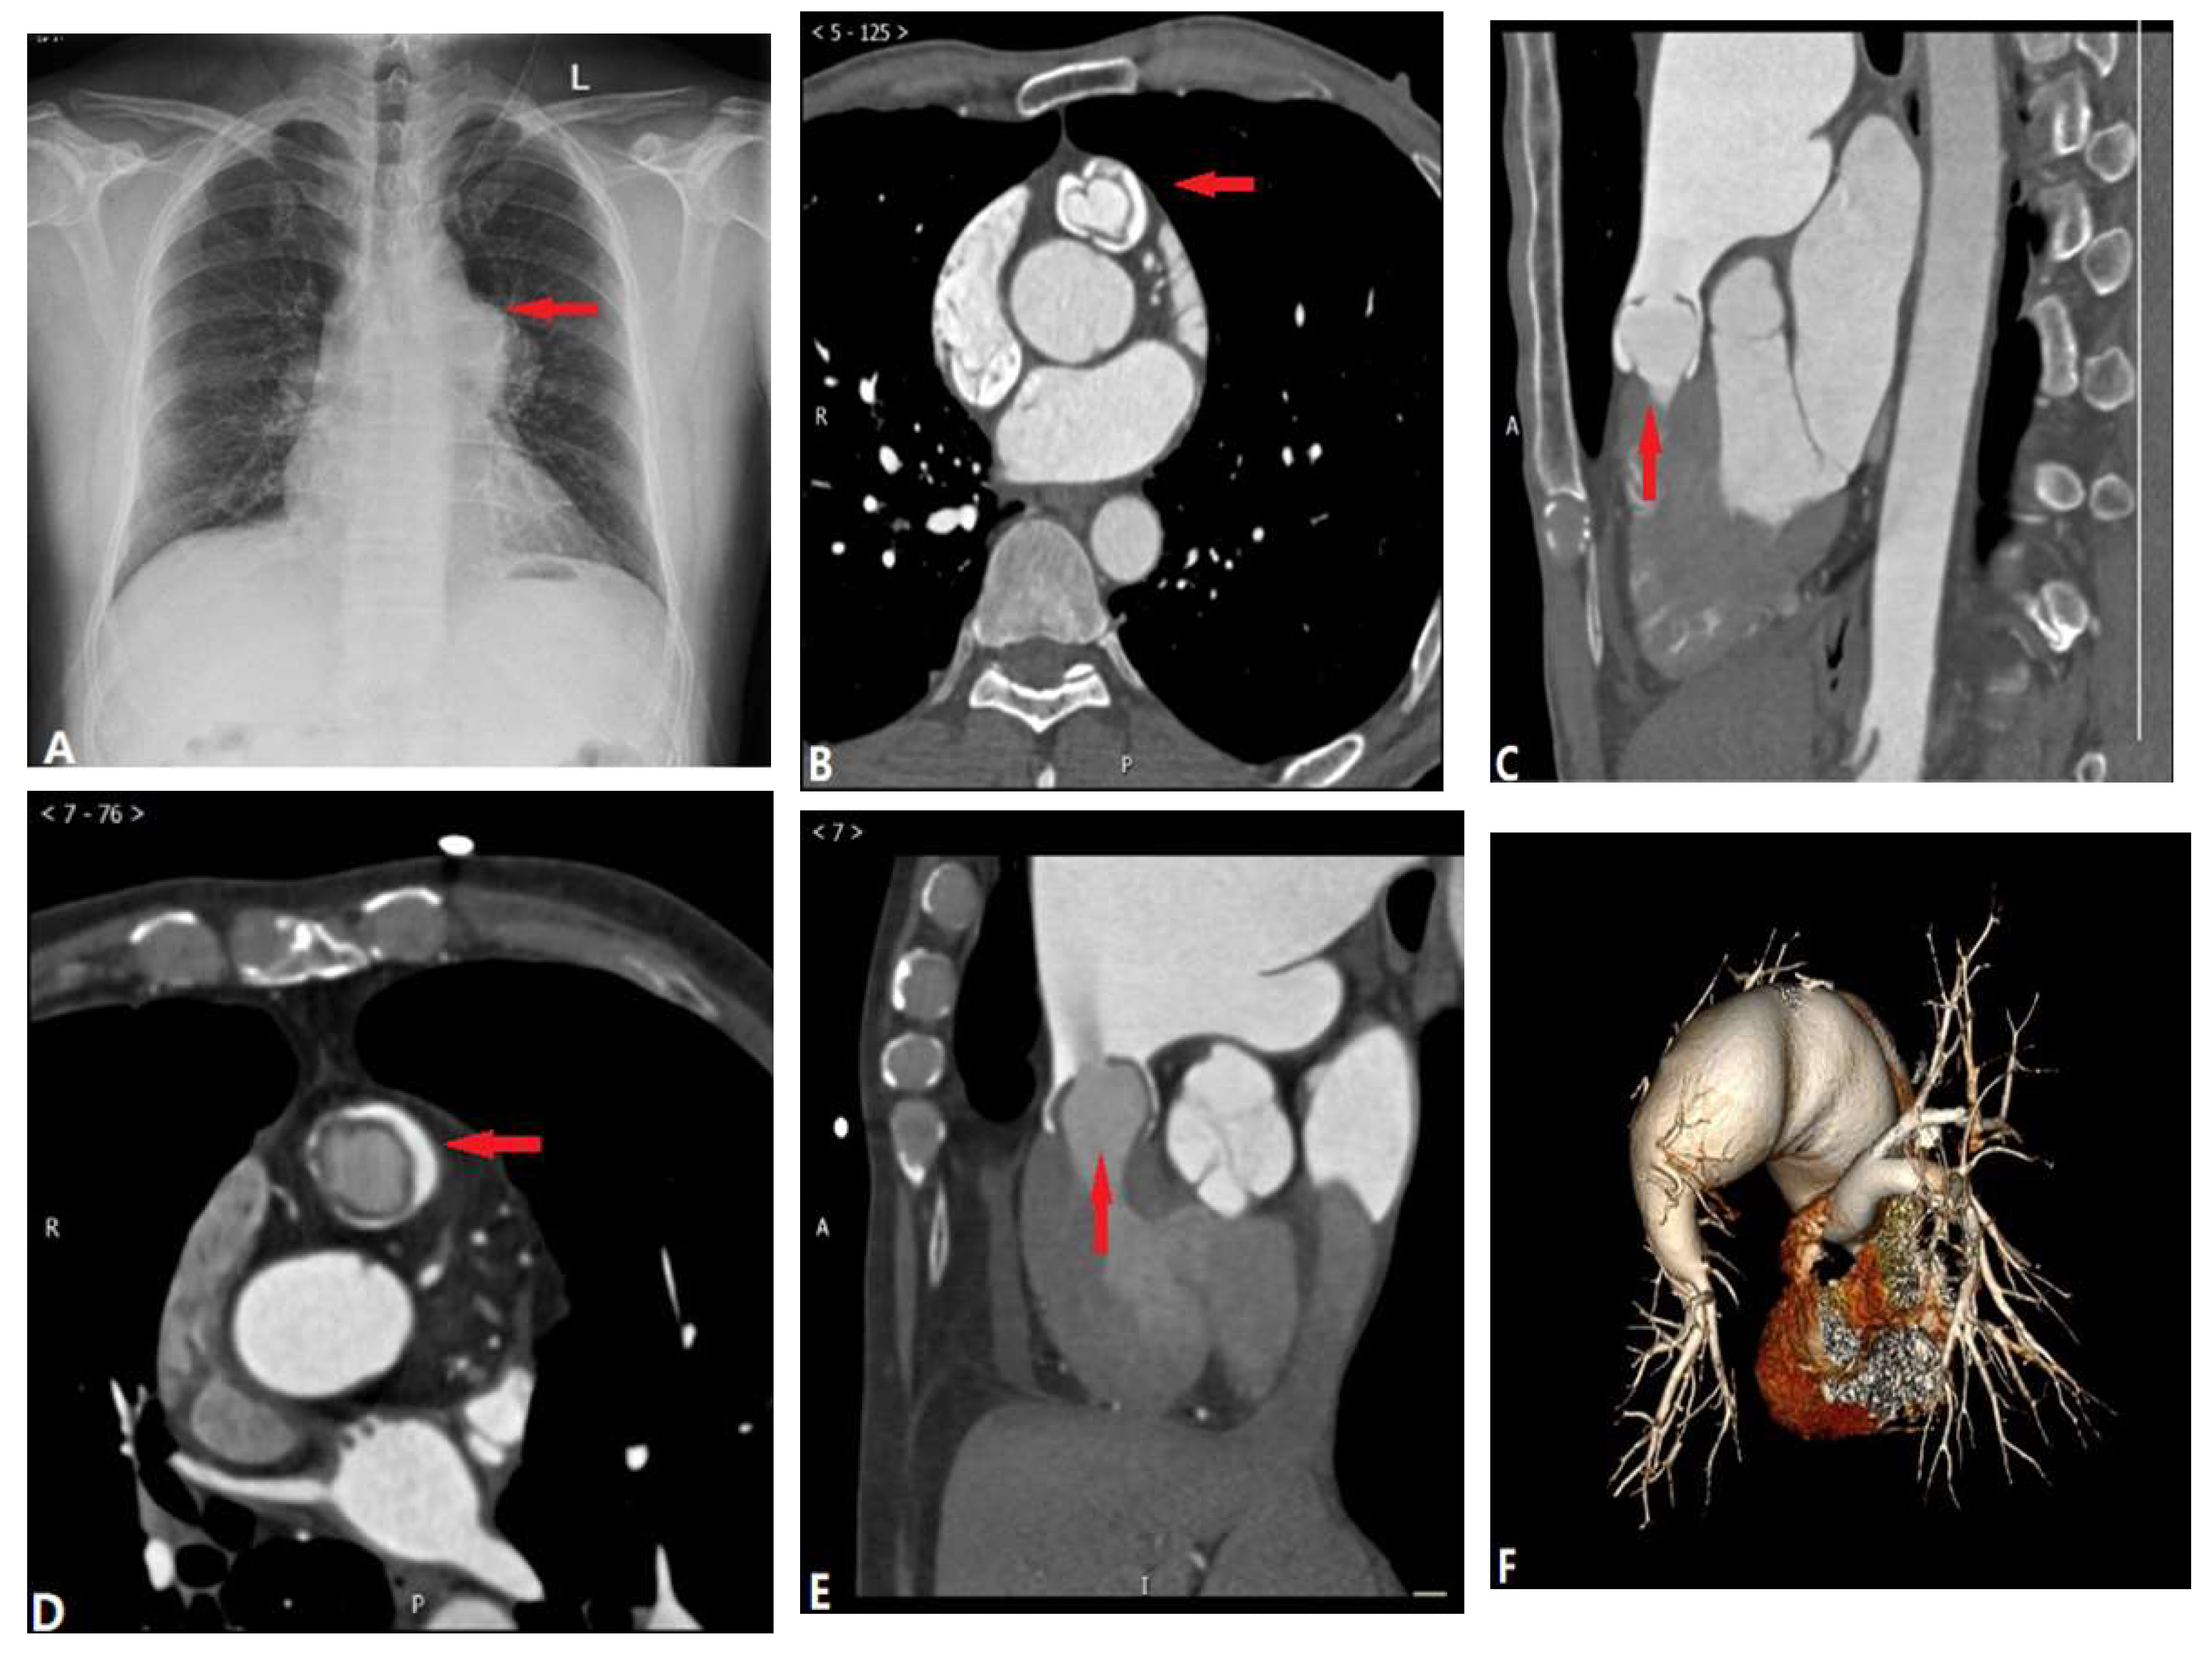

3.1.6. Pulmonary Artery Sarcoma

3.2. Vessel Wall Lesions